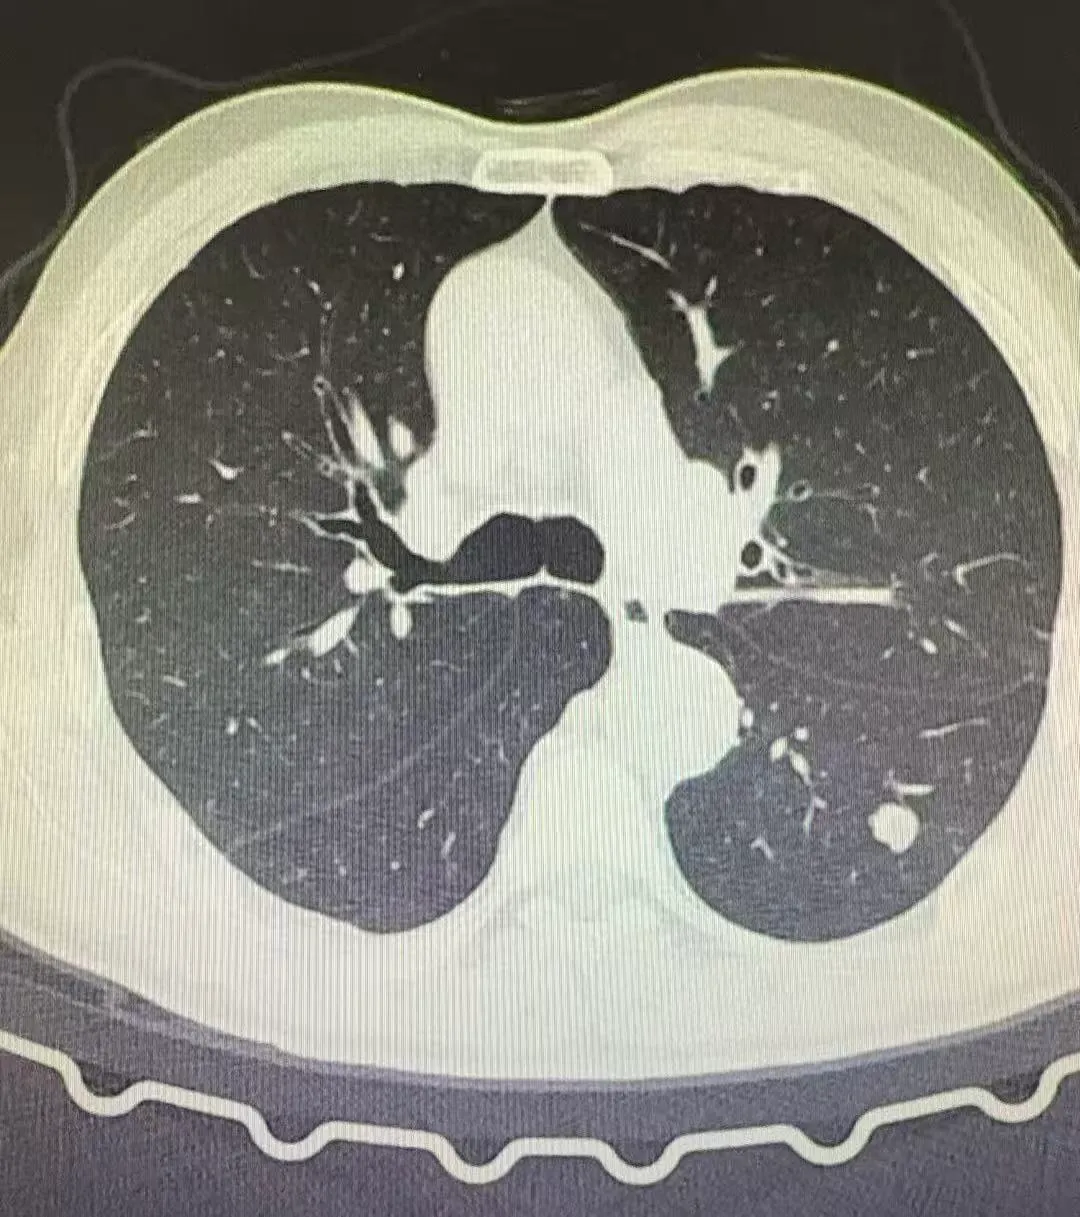

病例1:

患者公某,于当地医院查体发现左肺下叶肿物,大小约12mm,就诊我院拟行手术治疗,后经张振江主任阅读病史及综合分析后,考虑为良性结节,决定立即中止手术继续随访。后经患者两次随访观察,目前肺肿物大小较前无明显变化。

2025.06.04胸部CT